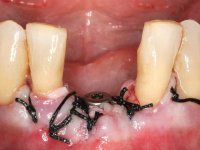

Female patient, 56 years-old, smoker. Teeth 41 and 31 with mobility grade III. Teeth 42 and 32 vital, with no mobility. After clinical and radiographic examination the extraction of central incisors was indicated.

Being an esthetic area it was decided to do an immediate splint of the crowns 41 and 31 to the adjacent teeth with a metalic mesh bonded in the lingual surface.

• Extraction of teeth 41 and 31 keeping the crowns of the same teeth as a provisional situation.

Splinting of teeth 41 and 31 to the adjacente teeth with a metallic mesh allowed us to temporarily resolve the esthetic situation and simultaneously avoid the use of a removable prosthesis, during the healing of the sockets and also during the osteo-integration phase of the dental implant.